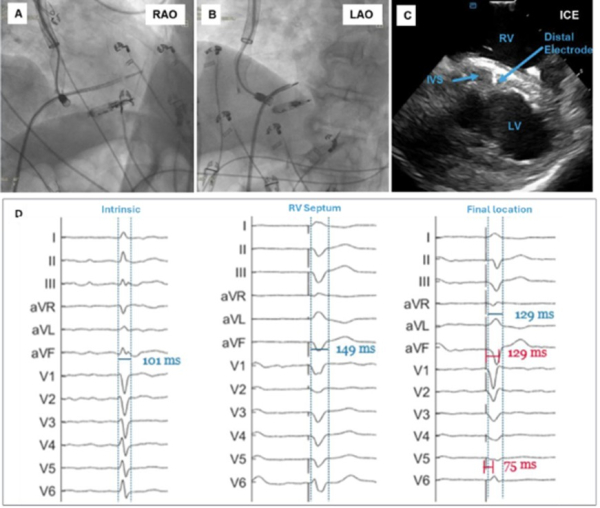

Le stimulateur de branche gauche sans sonde était inséré par voie jugulaire droite sous contrôle scopique, échographie intra cardiaque et injection de produit de contraste. Les mesures étaient faites en tether mode. Le dispositif était retiré à la fin de la procédure.

Figure 1